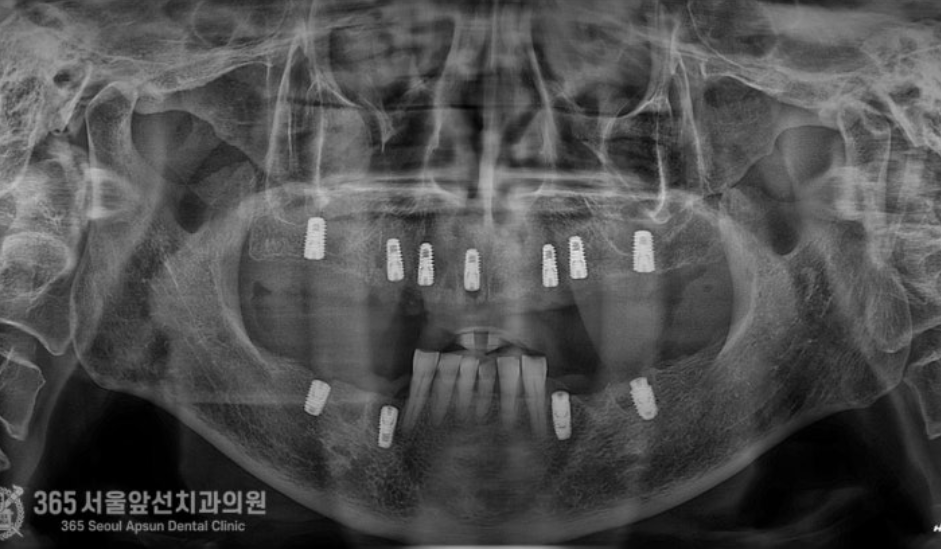

촬영일시 : 24.06.12 처음 내원 당시 엑스레이 사진입니다. 치아가 많이 없으시고 특히 어금니 쪽에는 뿌리끝에 염증이 많이 잡혀있어서 치아가 많이 불편하셨던 상태입니다.